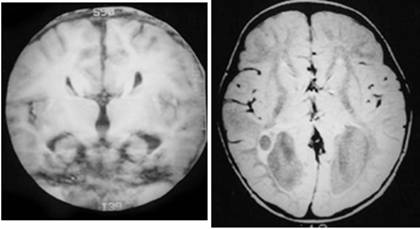

Figure 2

Clinical and image aspects of patient 2